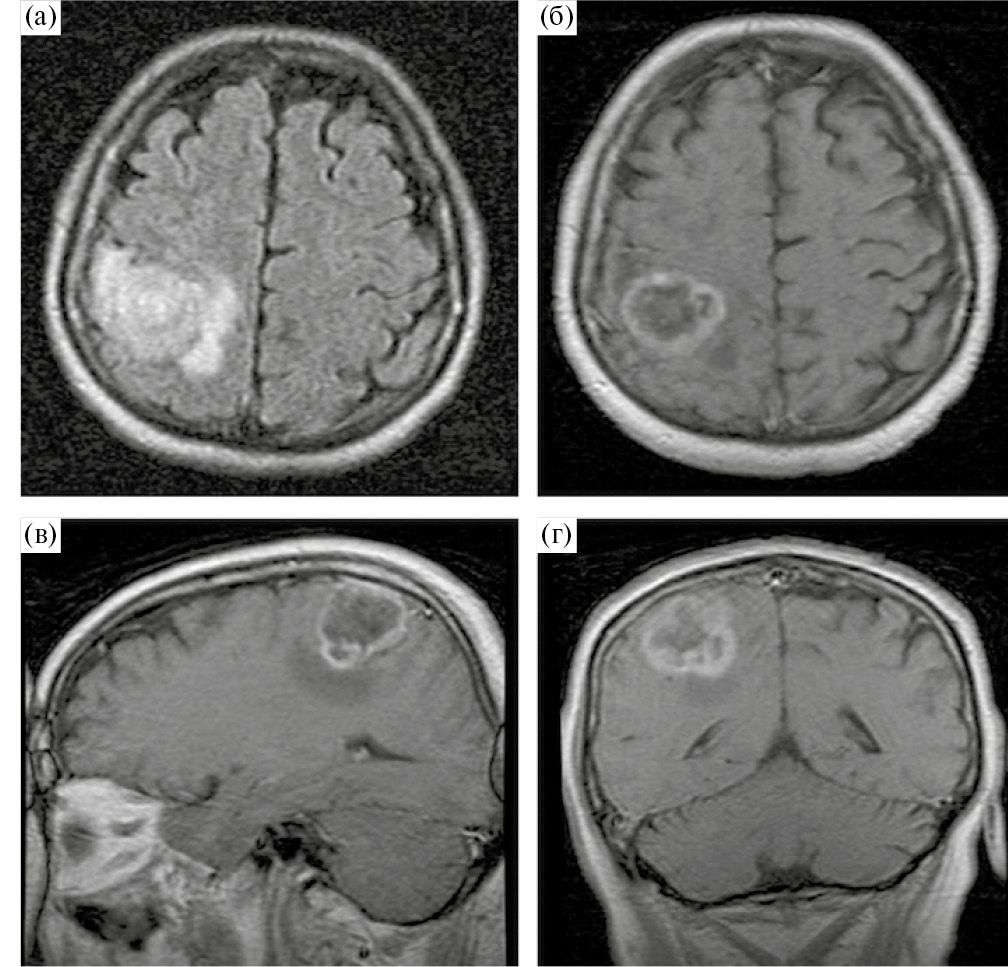

Аласенс (препарат 5-аминолевуленовой кислоты) вводился перорально за 2 ч до разреза ТМО из расчета 20 мг/кг. Из исследования были исключены 12 пациентов, у которых не отмечалось визуальной флуоресценции во время операции. Всем пациентам была проведена оценка мышечной силы до операции, на первые и седьмые сутки после хирургического лечения, выполнена предоперационная МРТ (Т1, Т2, Т2-FLAIR, DWI, T1+C, DTI) с определением расстояния от опухоли до КСТ и типа взаимоотношения между трактом и новообразованием. Было показано, что из 108 пациентов у 21 (19.4%) наблюдался интактный КСТ, у 43 (39.8%) – смещенный, у 34 (31.5%) – смещенный и инфильтрированный, у 8 (7.4%) – инфильтрированный, и только в одном наблюдении опухоль располагалась в структуре тракта, расщепляя его (рис. 1).

Рис. 1. (а) – пример интактного КСТ по данным ДТ-трактографии у пациента с глиобластомой. Тракты симметрично расположены и не отличаются значимо по объему. (б) – пример смещенного КСТ, по данным ДТ-трактографии у пациента с глиобластомой. Тракты не вовлечены в опухоль, однако положение их отличается. (в) – пример инфильрированного КСТ, по данным ДТ-трактографии у пациента с глиомой Grade IV. Несмотря на вовлечение КСТ в опухоль, по данным Т2-FLAIR отмечается правильное, симметричное положение тракта. (г) – пример смещенного и инфильтрированного КСТ, по данным ДТ-трактографии у пациента с глиобластомой. Тракты расположены асимметрично и вовлечены в зону отека-инфильтрации. (д) – пример расщепленного тракта у пациента с анапластической астроцитомой. Опухоль располагается внутри КСТ, расщепляя его волокна.

Fig. 1. Different types of relationship between the corticospinal tract and the tumor according to MR-tractography (intact, displaced, infiltrated, displaced and infiltrated, split).